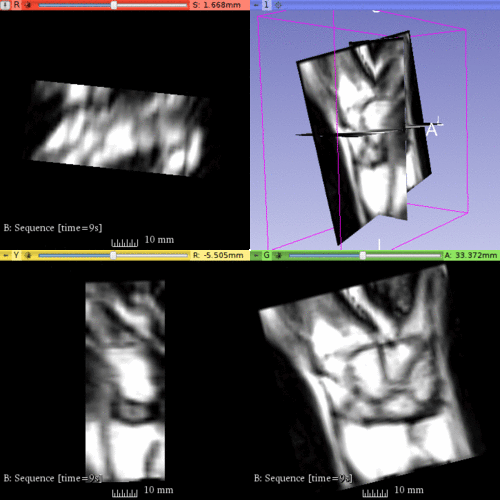

The goal of this project is to analyze wrist kinematics from a dynamic MRI sequence. Challenges include segmentation of wrist bones from relatively low resolution MRI with anisotropic voxels, and joint spatiotemporal modeling of extracted bones as a multi-object complex. |

Illustrations